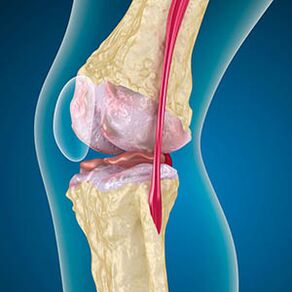

Pri artróze je chrupavka obložená okraje kostí alebo úplne chýba. Poškodené tkanivo nie je zdrojom bolesti, pretože nemá receptory. Zápal v blízkych štruktúrach spôsobuje charakteristické príznaky.

Telo pokračuje v regenerácii poškodených tkanív, ale chrupavka rastie nerovnomerne. V dôsledku toho sa tvoria nezrovnalosti, ktoré poškodzujú ďalšie prvky kĺbu. Povaha osteofytov je vysvetlená kompenzáciou hladkej kĺbovej chrupavky. Ďalšia verzia naznačuje, že rast „Spurs“ Je spojená s pokusom stabilizovať kĺb stredne alebo laterálne v dôsledku oslabenia svalov.

Rádiograf ukazuje prítomnosť osteofytov, zmena priestoru medzi kosťami femorálnych a holenných kostí, čo naznačuje stratu chrupavky v kolene. Niekedy X -Brey of the Knee kĺby vykazuje významné príznaky opotrebenia chrupavky, ale pacienti nemajú významnú bolesť.Naopak, artróza prvého štádia môže narušiť funkciu kolena, pretože príčinou bolesti sú hypotonické svaly.